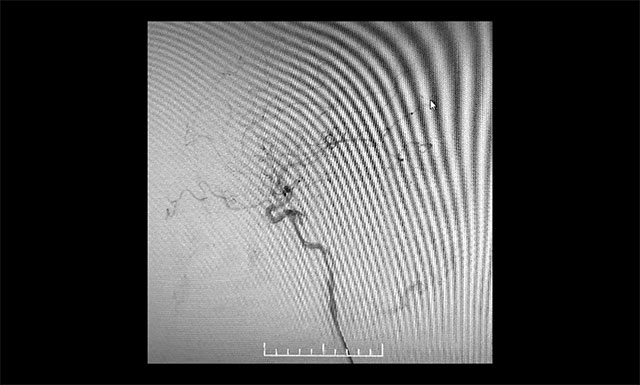

微導(dǎo)管造影確認(rèn)后,注入 Onyx 18膠7.5ml

▲ 微導(dǎo)管造影確認(rèn)后,注入 Onyx 18膠7.5ml